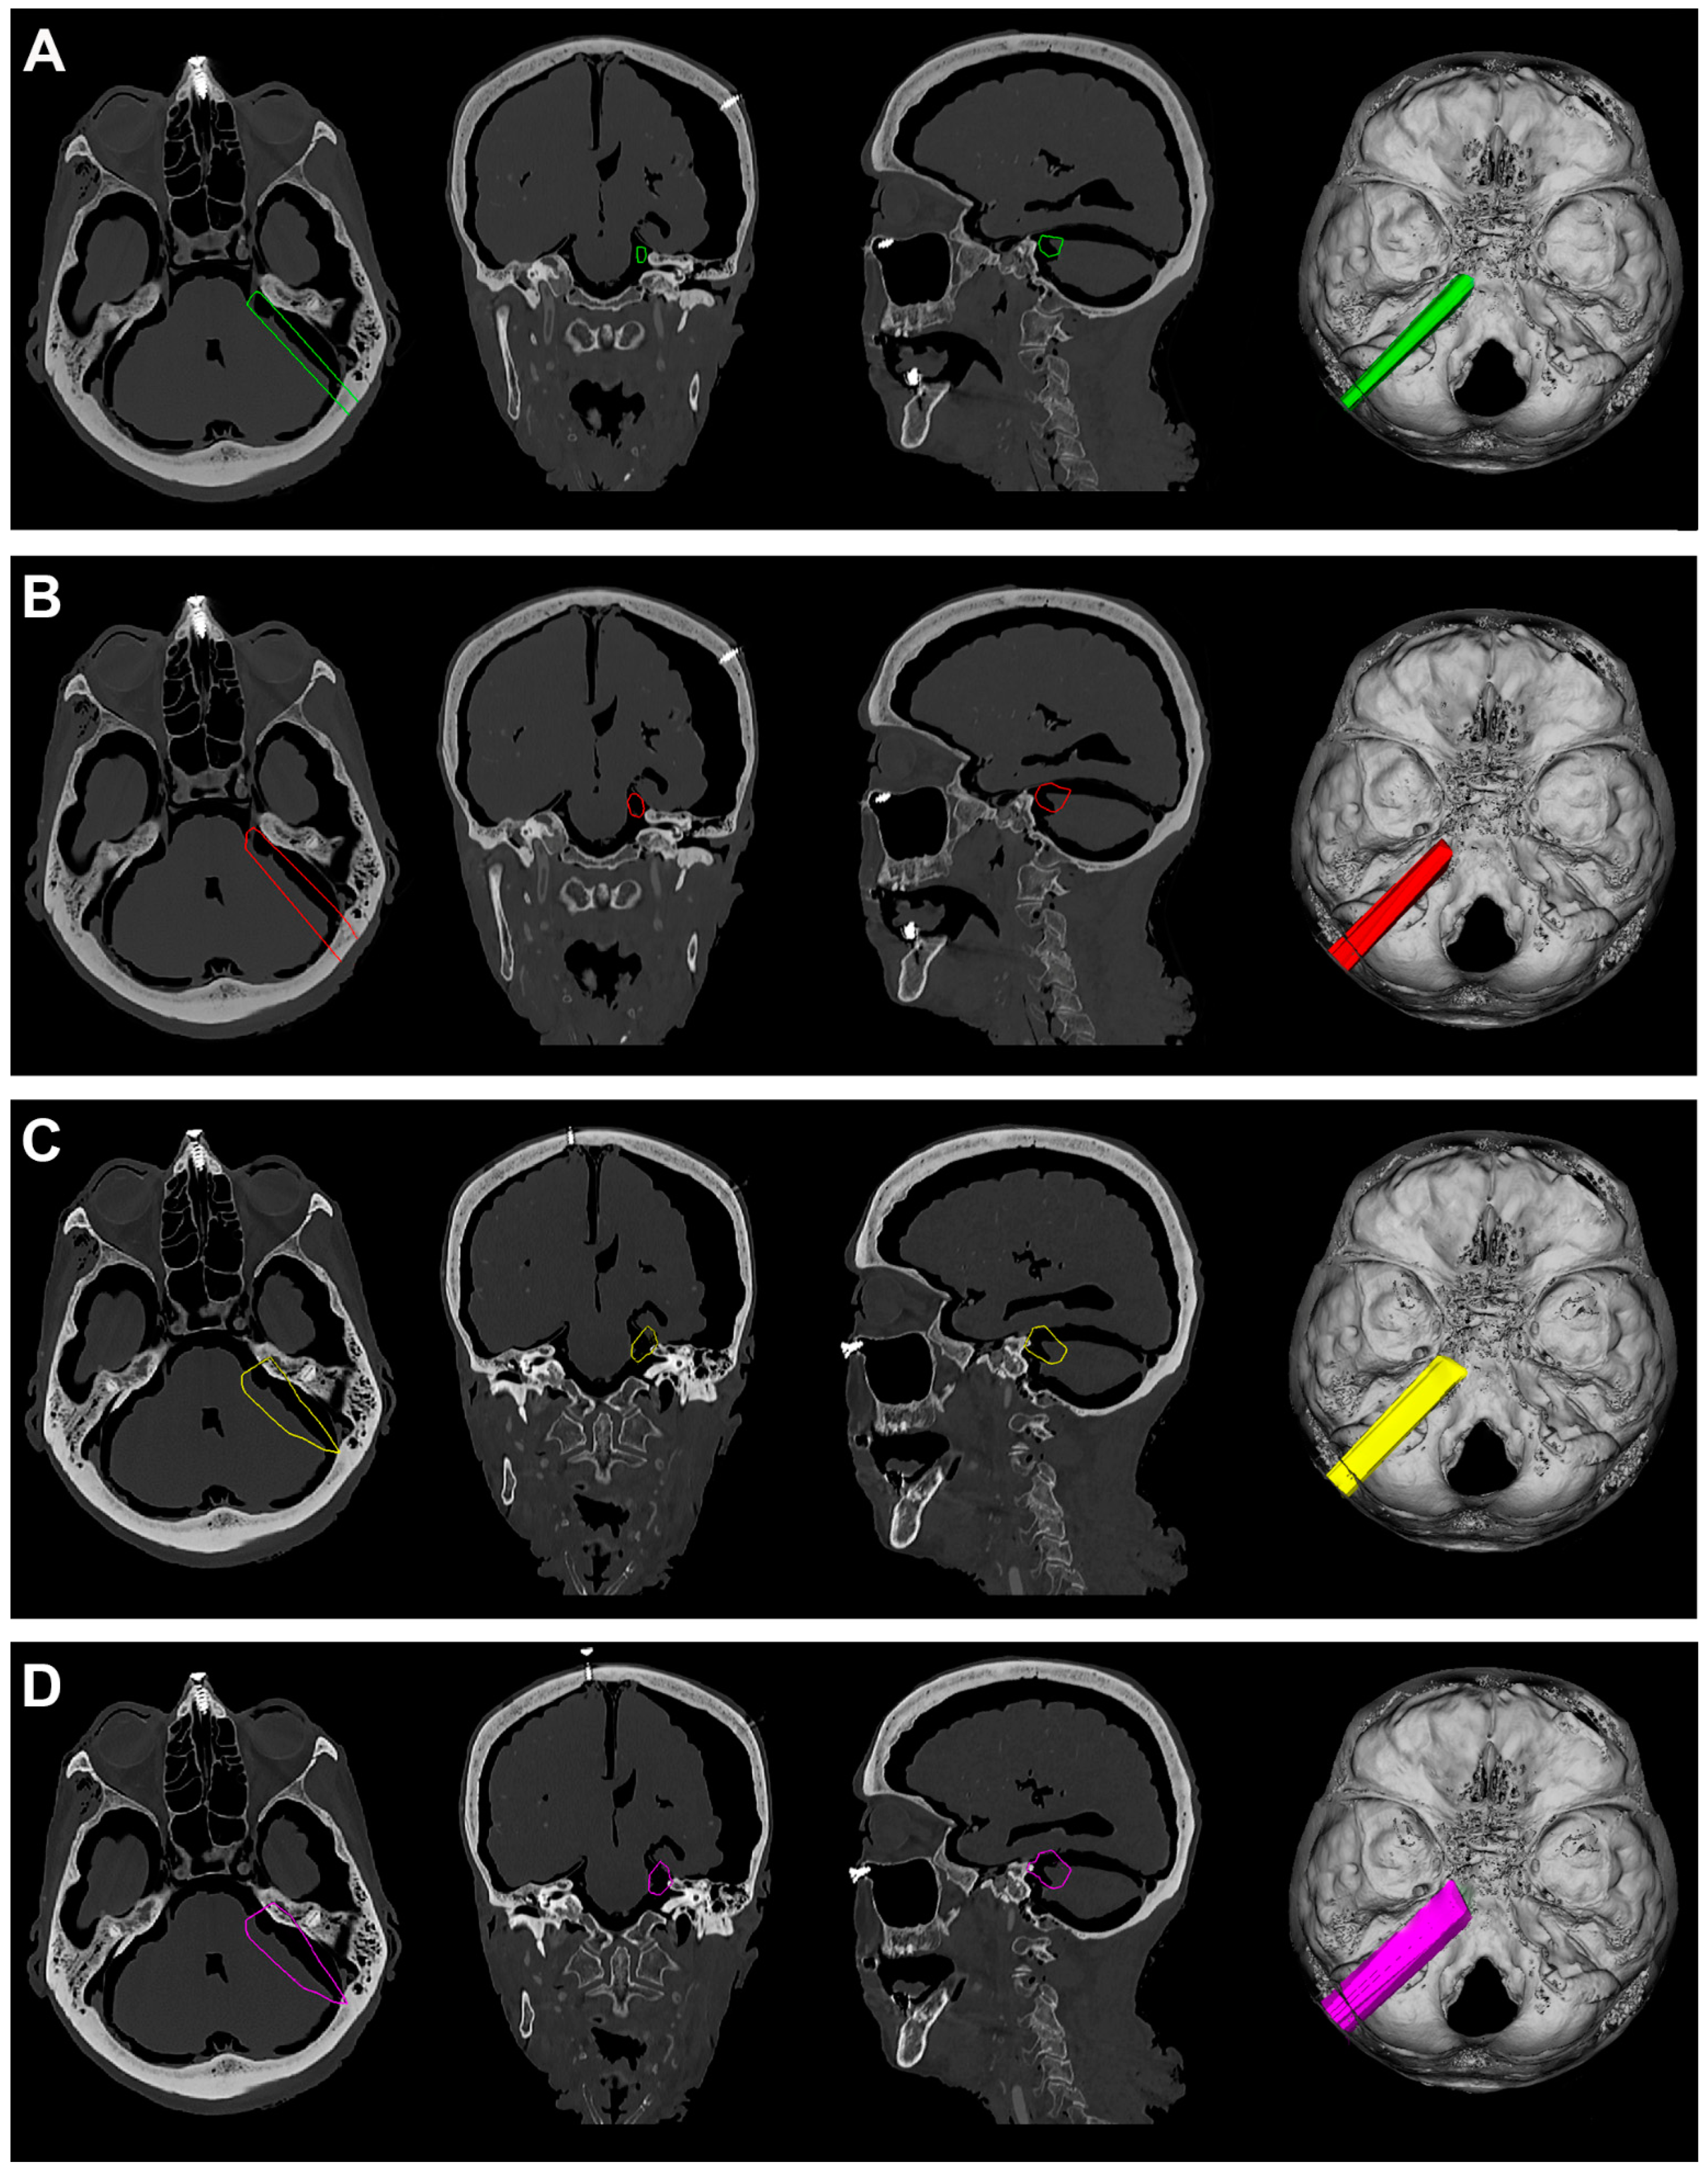

Figure 6.

(A). Exemplificative screenshot from Approach Viewer of the PTA with 10 mm of retraction. (B). Exemplificative screenshot from Approach Viewer of the PTA with 15 mm of retraction. (C). Exemplificative screenshot from Approach Viewer of the FTOZ with 10 mm of retraction. (D). Exemplificative screenshot from Approach Viewer of the FTOZ with 15 mm of retraction.